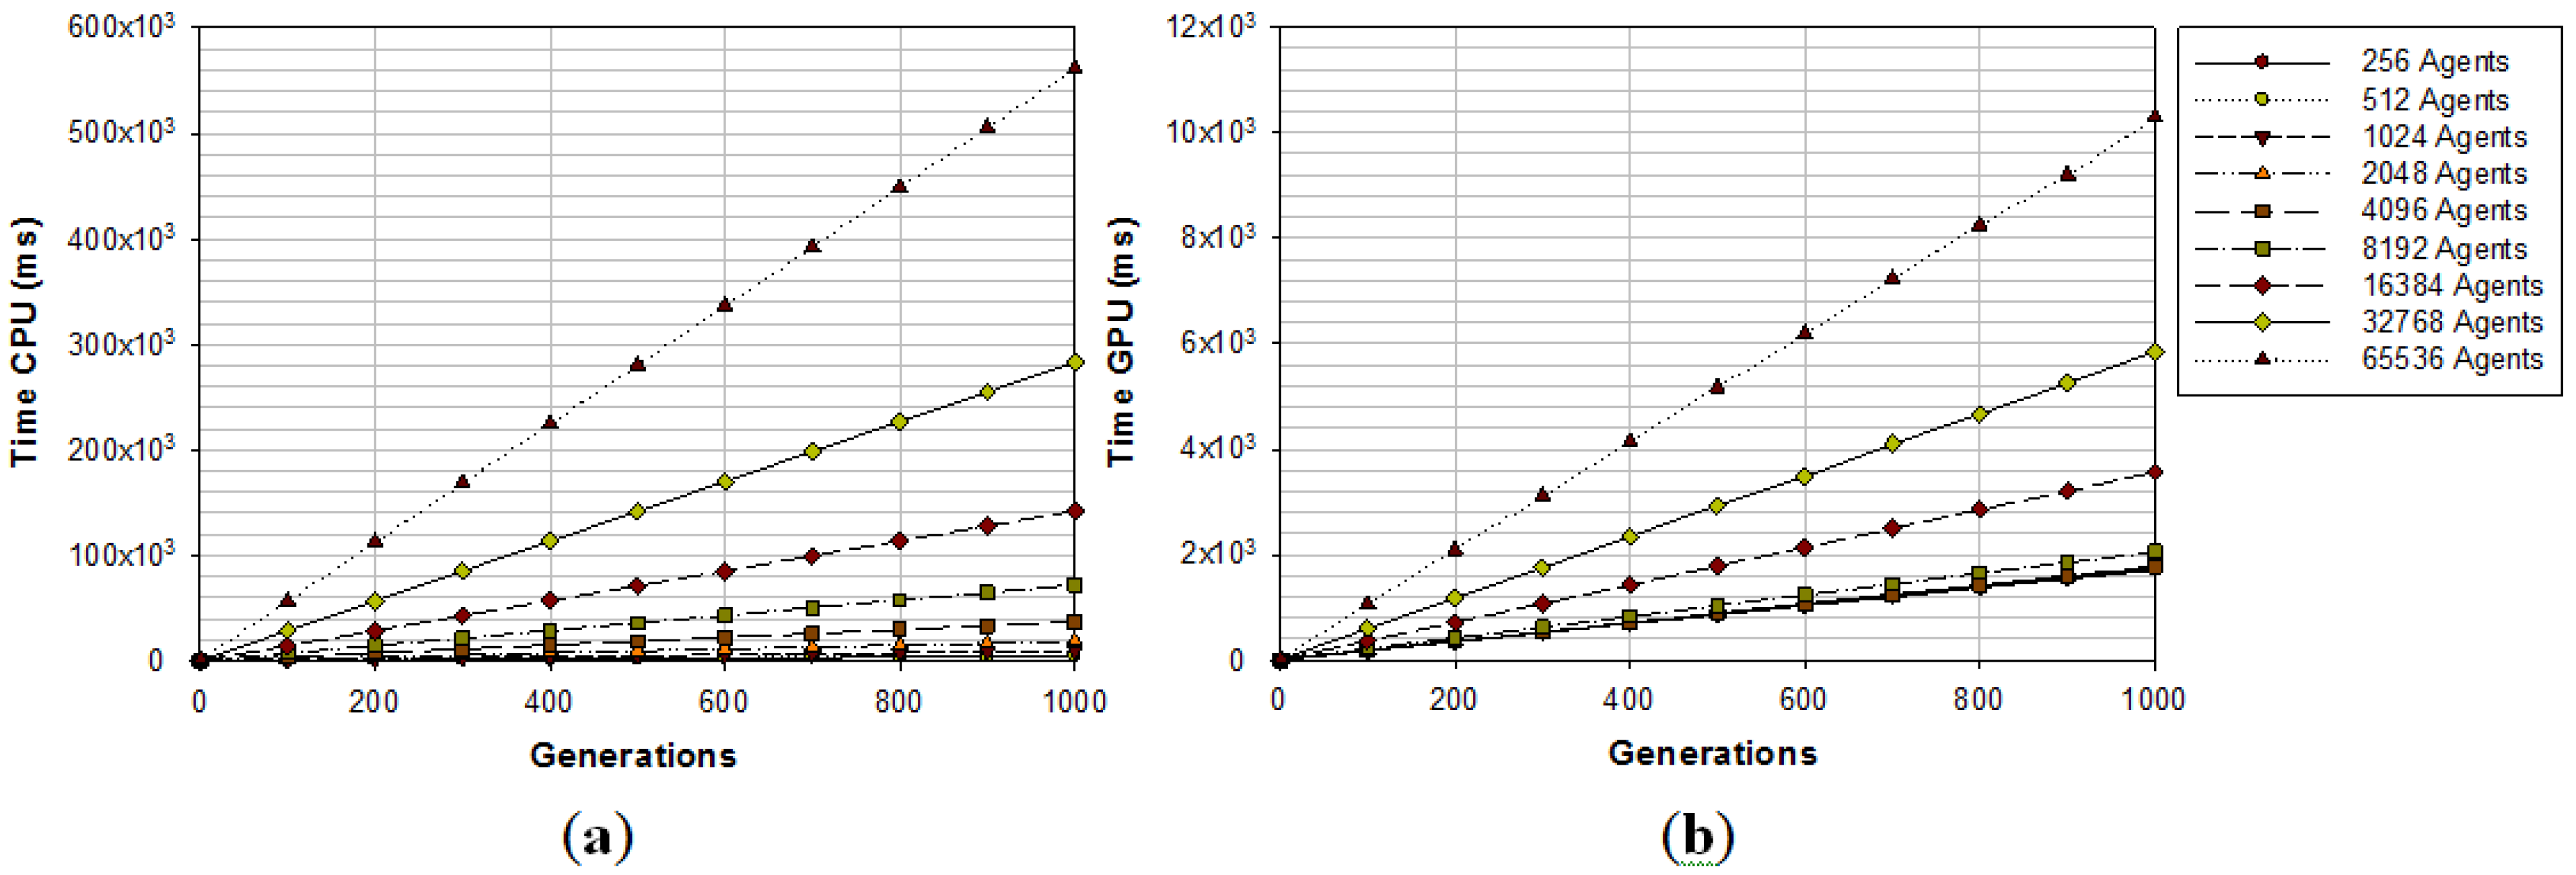

2.3. GPU Implementation

| Method | GPU Time | CPU (8 cores) Time |

|---|---|---|

| SRAD (AOS)5 Iterations | 7.65 ms | 13.58 ms |

| FRS | 3.78 ms | - |

| Pixel Orientation | 1.14 ms | 6.95 ms |

| Non-Max Suppression | 0.16 ms | 2.29 ms |

| LIP-Sobel Gradient | 0.11 ms | 1.42 ms |